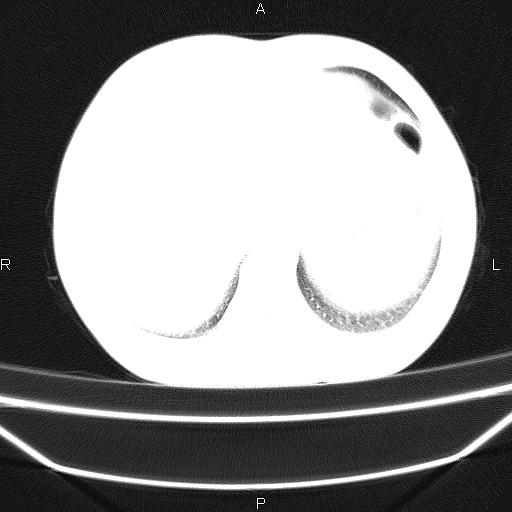

标题: CT26599:男,40岁。间断发热,咳嗽二十余日。体温最高达38.9 [打印本页]

标题: CT26599:男,40岁。间断发热,咳嗽二十余日。体温最高达38.9

患者,男,40岁。间断发热,咳嗽二十余日。体温最高达38.9° 在当地诊所抗炎治疗三天后体温降至正常,患者自行停药。今又发热。胸片示,左下肺阴影。

标题: 左下肺片状高密度影

左下肺片状高密度影,境界模糊,密度不均,考虑感染性病变可能性大,建议抗炎治疗后复查。左肺门增大,不除外占位性病变,必要时支气管镜检。